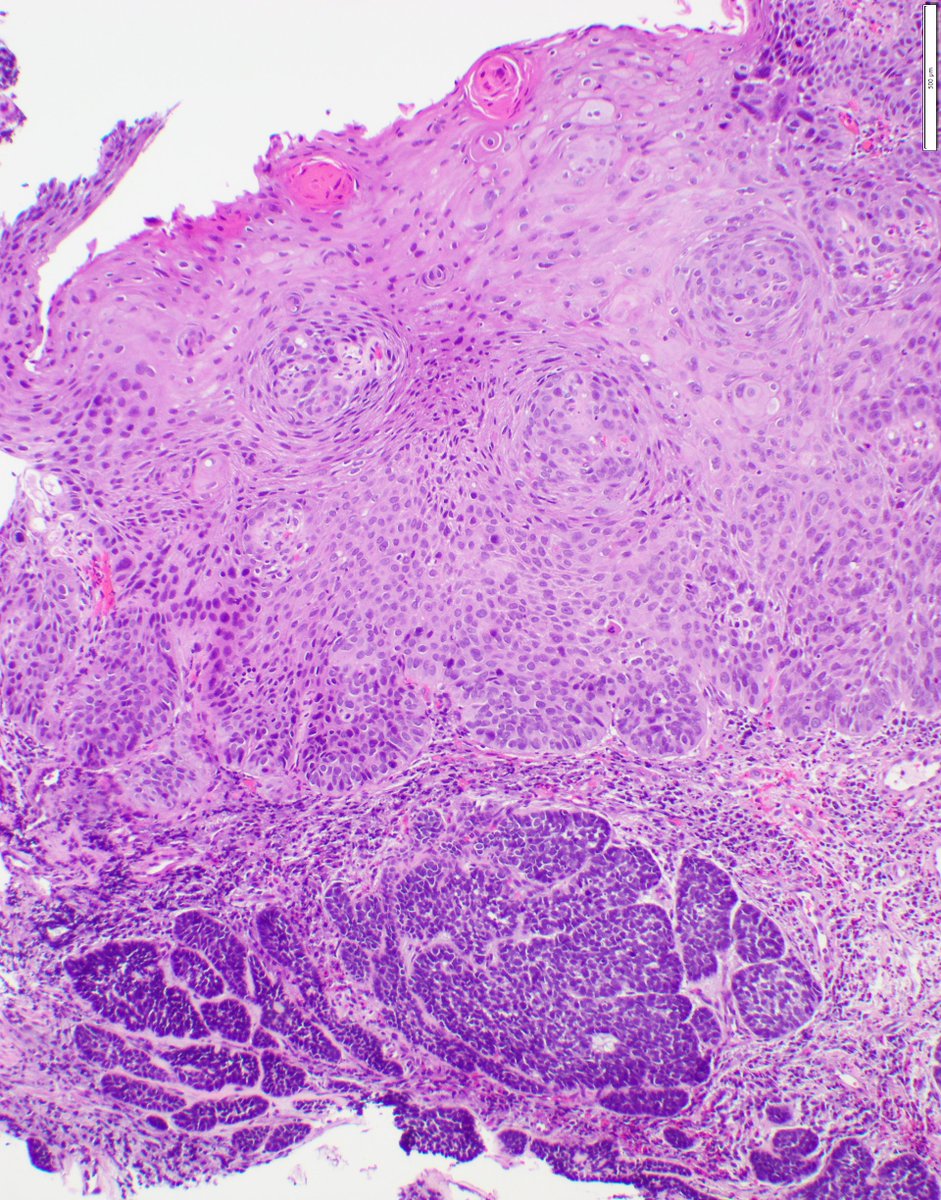

Atypical polypoid adenomyoma: biphasic lesion with crowded, architecturally complex endometrioid glands showing cytologic atypia, embedded in a myomatous stroma. Don’t overcall as carcinoma #PathTwitter #GYNpath